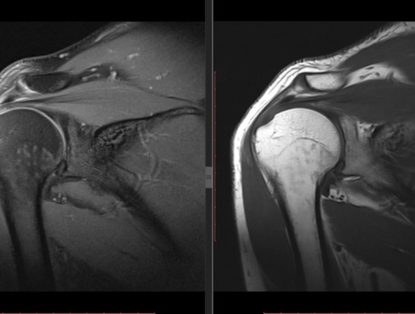

Injuries That Need Musculoskeletal Imaging

Musculoskeletal imaging is a painless procedure that includes the use of CT, MRI, ultrasound, or X-ray and gives radiologists a deep look into the ...